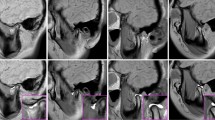

Figure 3 visually illustrates the outcomes of segmenting the TMJ components. The demarcated regions for the temporal bone and condyle were predominantly accurate, with minimal aberrations observed peripherally. The segmentation of the disc component appeared to be slightly indistinct; however, its spatial placement was accurately discerned, demonstrating that this model could play a significant role in diagnosing disc displacement. Concurrently, the background delineation was notably accurate. Additionally, Fig. 4 depicts a representative TMJ disc displacement, indicating the relative positioning of the joint's components, while Fig. 5 exhibits a TMJ osteoarthritis example, underlining the condylar morphology but with a slightly subdued edge definition in comparison to the reference.